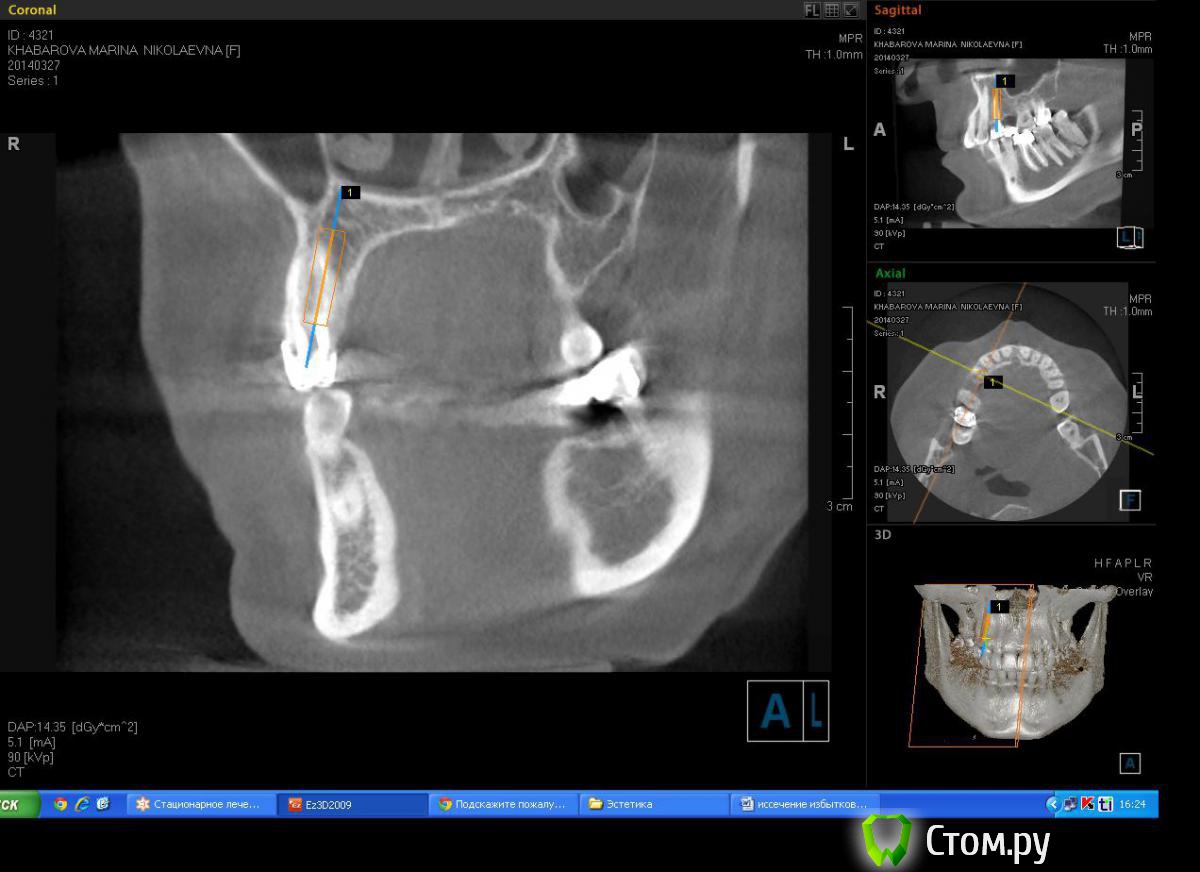

Milanomoda Опубликовано 22 апреля, 2014 Поделиться Опубликовано 22 апреля, 2014 Здравствуйте, уважаемые коллеги. Вообщем обратилась за помощью пациентка - в области 14 зуб, от него консоль на 15, посоветовавшись с ортопедом, приняли решение удалить 14 зуб и одномоментно в лунку имплант, в это же посещение имплантация в области 15. Подскажите пожалуйста с тактикой, можно ли в данном случае рассматривать одномоментную методику имплантации ? Заранаее с пасибо ) Снимки КТ прикладываю. Ссылка на комментарий

Milanomoda Опубликовано 22 апреля, 2014 Автор Поделиться Опубликовано 22 апреля, 2014 Имплантацию в районе 14 зуба планирую ставить в область язычного корня, только вот вопросик такой, при одномоментном протоколе на сколько примерно заглублять нужно будет имплант? Ссылка на комментарий

Milanomoda Опубликовано 22 апреля, 2014 Автор Поделиться Опубликовано 22 апреля, 2014 Картина с планируемым 4.2 х 16 мм имплантом в области 14. Ссылка на комментарий